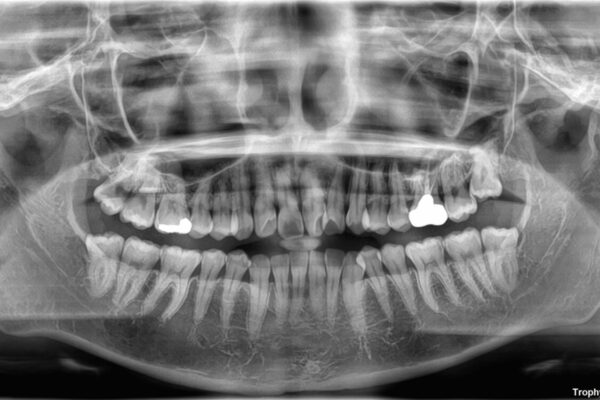

治療方法としては、装置の目立ちにくさと費用面のバランスを考慮して、プラスチック製のクリアブラケットとメタルワイヤーを組み合わせた矯正装置を使用することにしました。

また、上顎前歯の重なっていた部分にはむし歯が見つかり、治療中に適切な処置を行っています。

治療途中

• 前歯のねじれ・ガタガタを10か月で改善!20代女性の矯正治療|クリアブラケットでむし歯になりにくい歯並びへ改善 治療途中画像